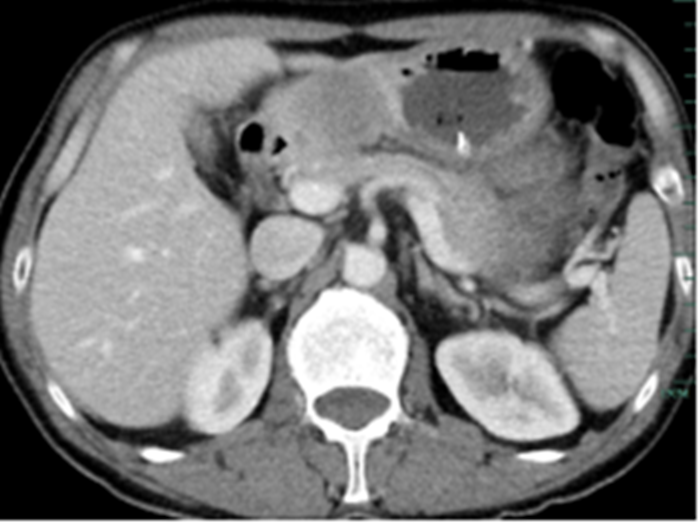

住院后經(jīng)胸腹部CT檢查,提示周先生胃部巨大腫塊穿破胃腔,可能累及到結(jié)腸,同時(shí)合并有胃旁淋巴結(jié)轉(zhuǎn)移、肝臟的轉(zhuǎn)移??吹竭@個(gè)檢查報(bào)告后,周先生和他的愛人一下子就泣不成聲了。

治療前的腹部CT提示胃